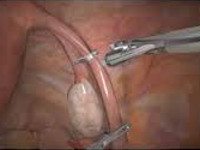

Стерилизация женщин. Хирургический метод контрацепции, который предназначен для искусственного блокирования проходимости маточных труб и предотвращения слияния яйцеклетки со спермой. Стерилизация женщины может быть сделана путем перевязки, электрокоагуляции, разрезания маточных труб специальными брекетами Операция по стерилизации женщины может быть выполнена минилапаротомным, лапароскопическим или трансвагинальным доступом. Результат контрацепции различных методов стерилизации для женщин составляет 99,6-99,8%.

Методы механической стерилизации включают в себя блокирование маточных труб специальными кольцами и зажимами (зажимы Filshi, пружинные зажимы Халка-Вульфа). Механические устройства накладываются на трубку, начиная с 1-2 см от матки. Преимущество механических методов стерилизации женщин заключается в меньшем повреждении тканей трубы, что облегчает проведение реконструктивных процедур, когда необходимо восстановить фертильность. В качестве метода стерилизации используется коагуляция маточных труб, введение специальных колпачков или химических агентов, вызывающих рубцовый стеноз труб.